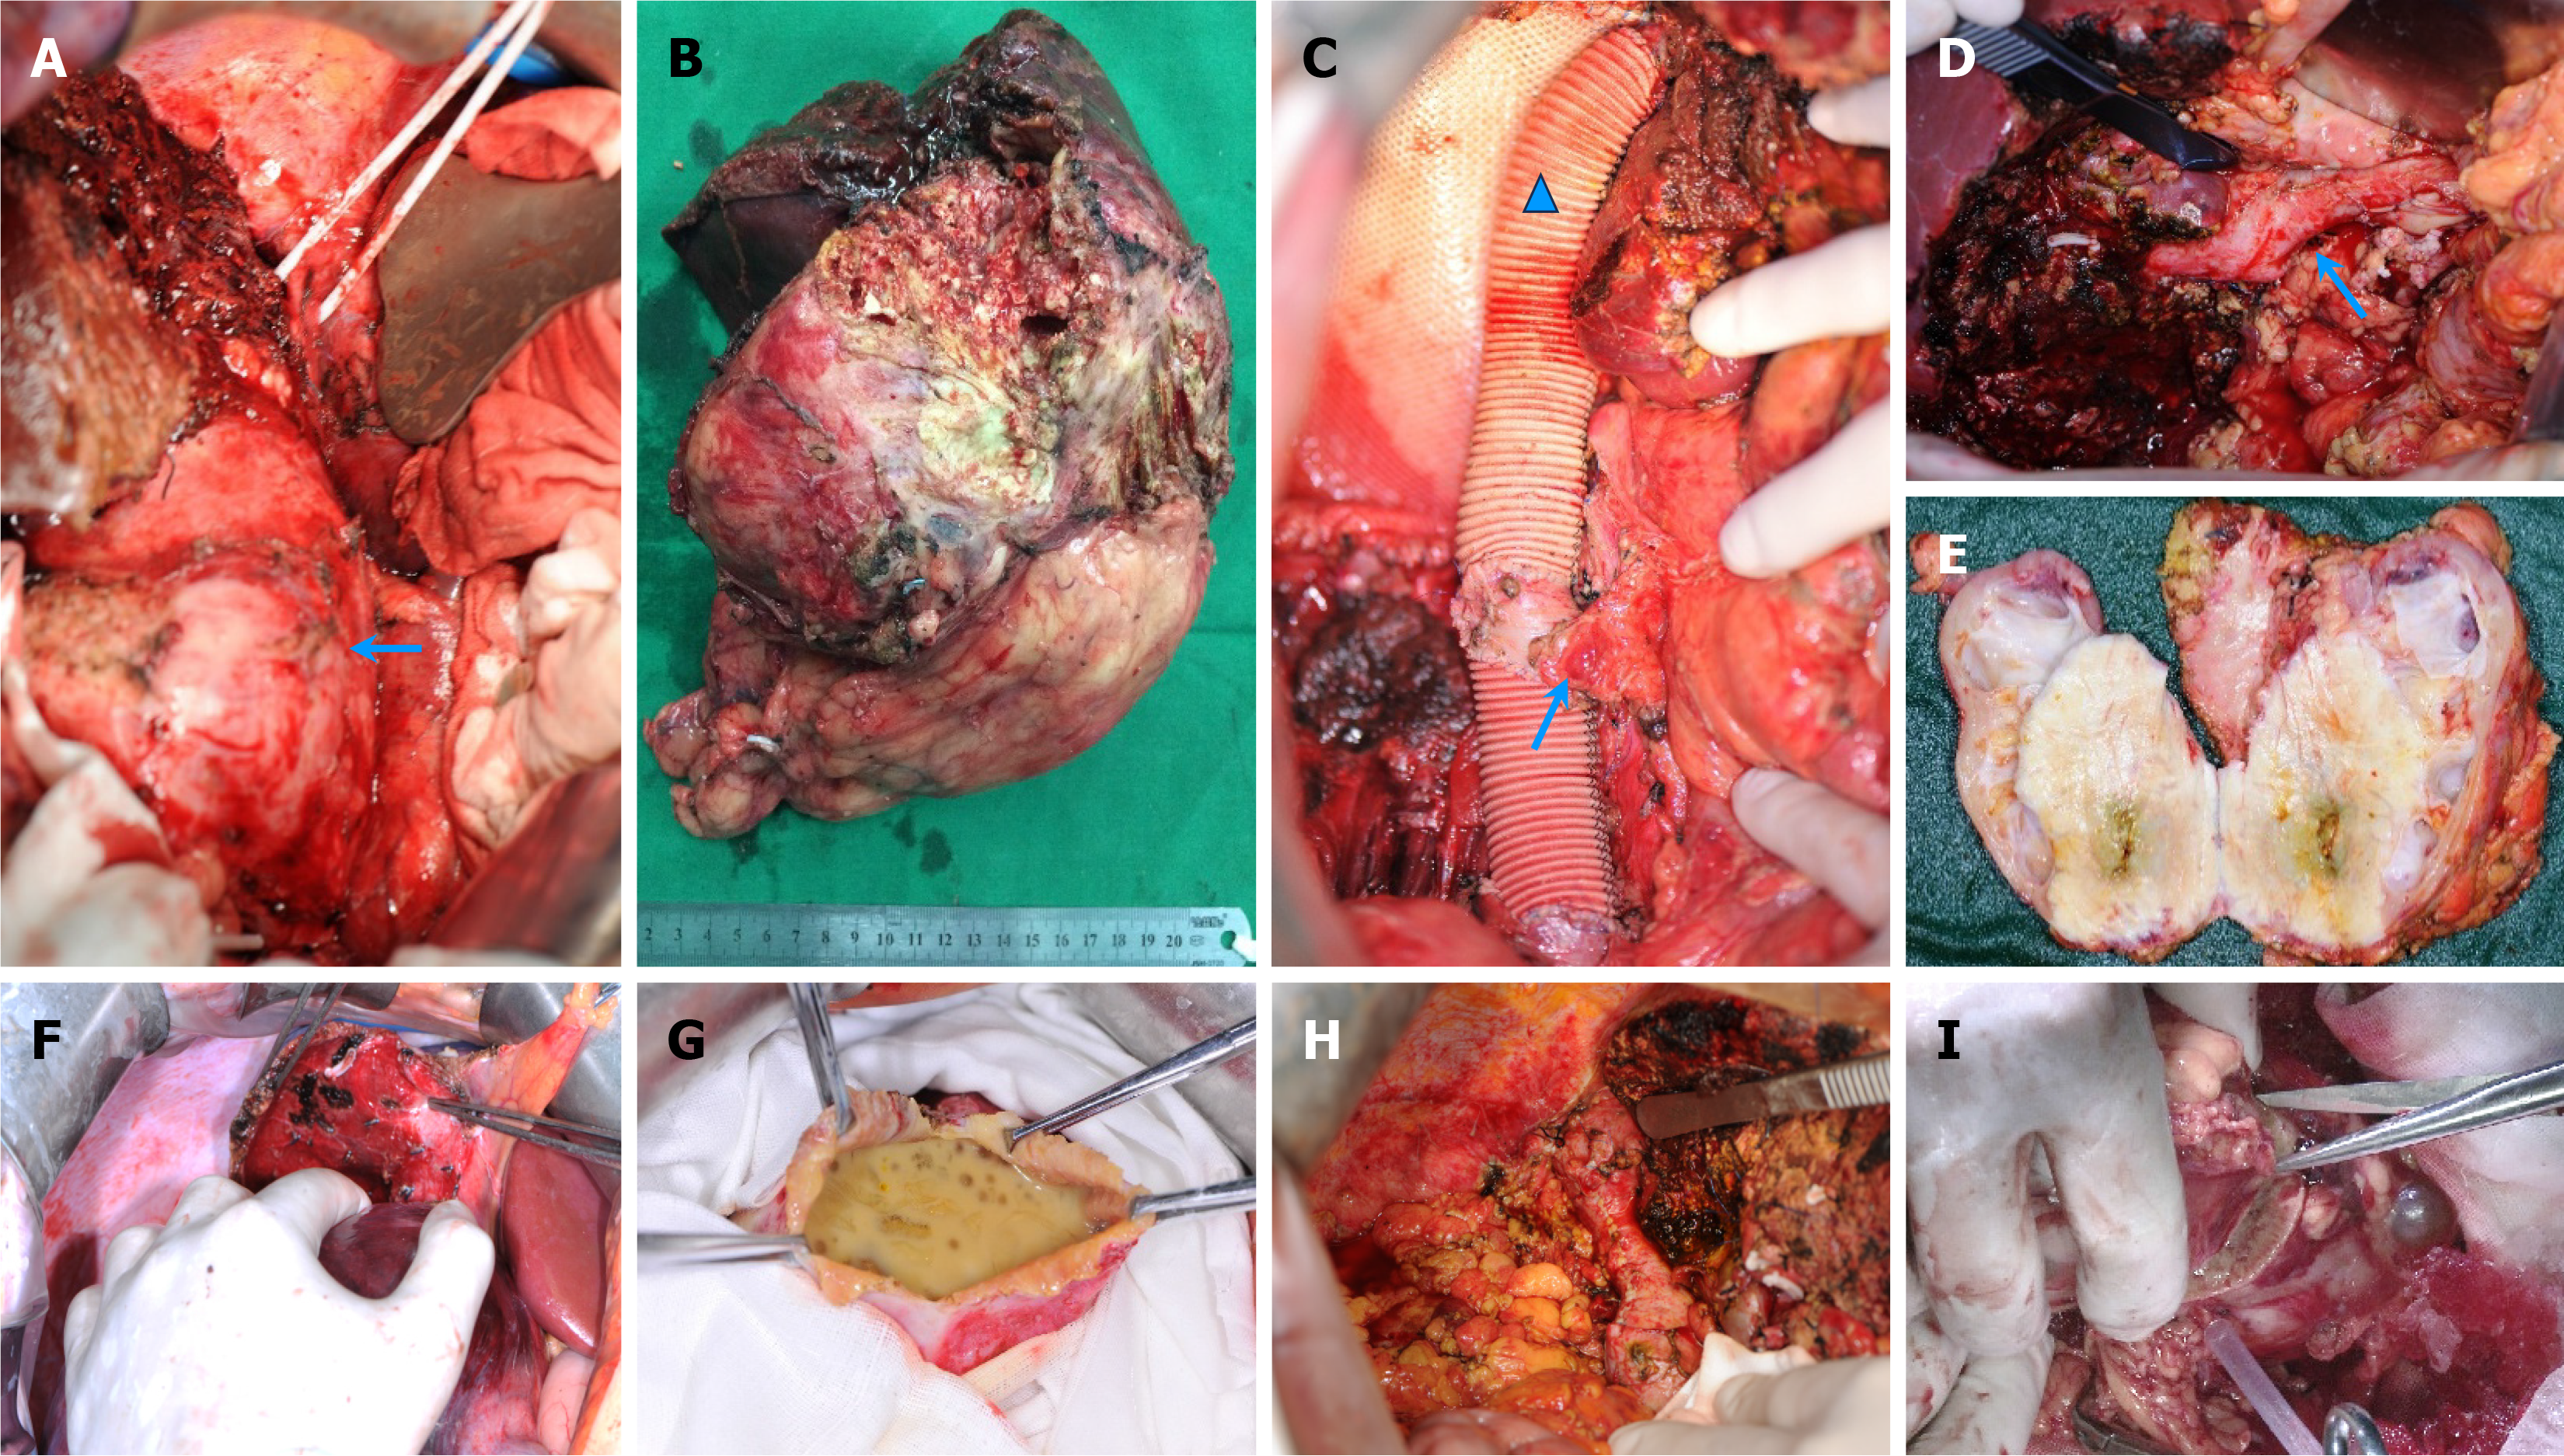

Figure 4 Surgical observations.

A-E: En bloc resection of the right hemiliver and right kidney (arrow) (A and B), extended prosthetic replacement of the diseased inferior vena cava, sutured and repaired blood vessels (arrow) and artificial blood vessels (triangle) (C) or repair via sutures (D), and (E) near-complete occupation of renal tissue were observed in alveolar echinococcosis cases; F and G: Total cystectomy (F) and open cystectomy (G) were predominantly employed in cystic echinococcosis (CE) subjects; H and I: Additionally, procedures such as inferior vena cava (arrow) repair with sutures (H) and partial nephrectomy (I) were required in select CE cases.